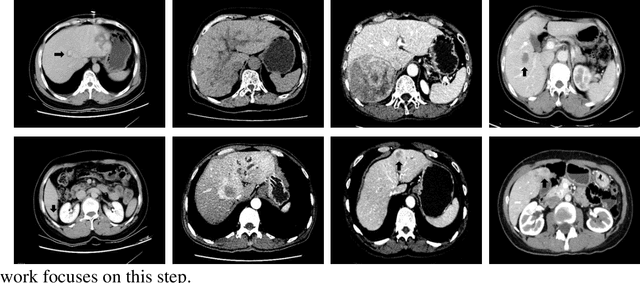

Figure 1 for Delving Deep into Liver Focal Lesion Detection: A Preliminary Study

Figure 2 for Delving Deep into Liver Focal Lesion Detection: A Preliminary Study

Figure 3 for Delving Deep into Liver Focal Lesion Detection: A Preliminary Study

Figure 4 for Delving Deep into Liver Focal Lesion Detection: A Preliminary Study